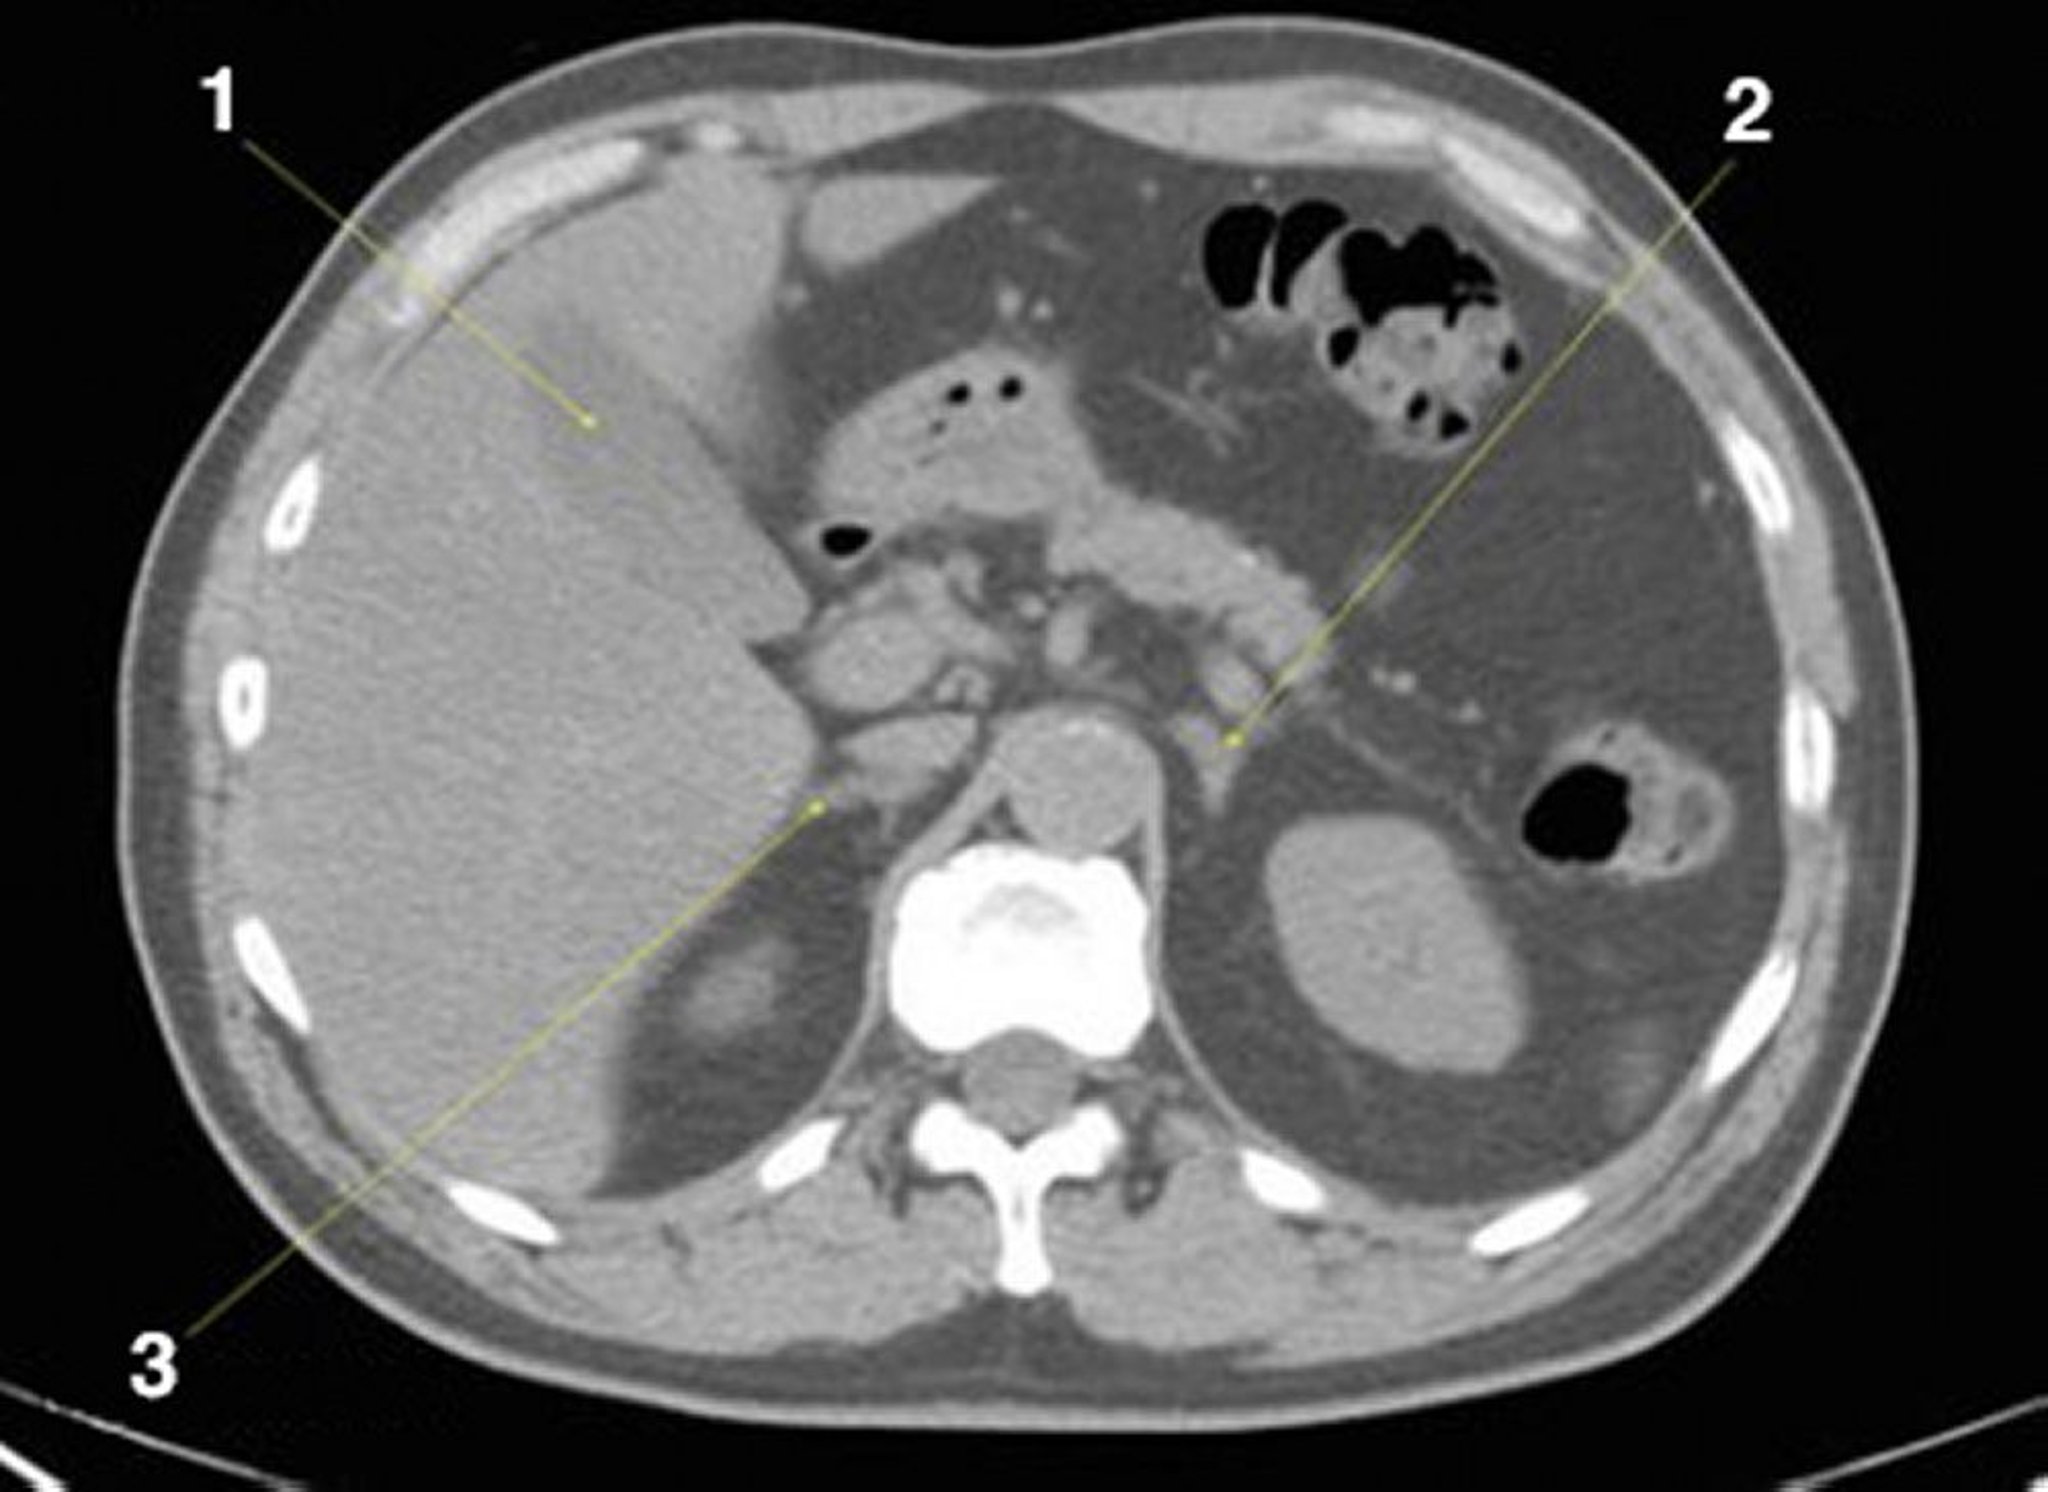

КТ брюшной полости и таза без контраста, демонстрирующая нормальную анатомию (слайд 8)

1 = желчный пузырь; 2 = левый надпочечник; 3 = правый надпочечник.